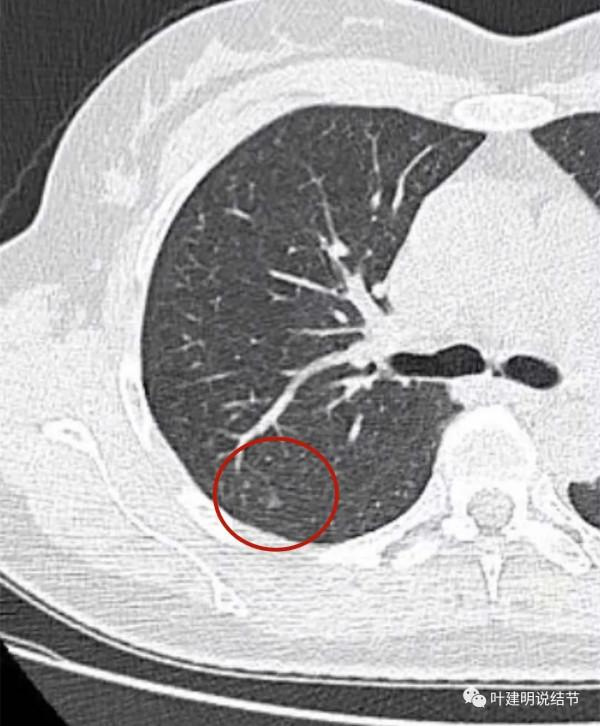

金華的某A,是我同學的大姨子,前段日子因為同學的愛人查出肺結節是早期肺癌,所以她姐姐記起來2年前也查出有肺結節,但沒有複查過,怕也得肺癌,所以到我門診來複查。我們先來看她平掃的CT影象:

右肺上葉後段磨玻璃結節

感覺是混合磨玻璃,而且密度偏高

見邊緣不光整,似有細毛刺

整體輪廓清楚

有微血管徵

胸腔有輕微牽拉

從平掃看,病灶雖然小,但就不舒服,極可能是惡性的。我們再來看她其餘部位還有小結節: